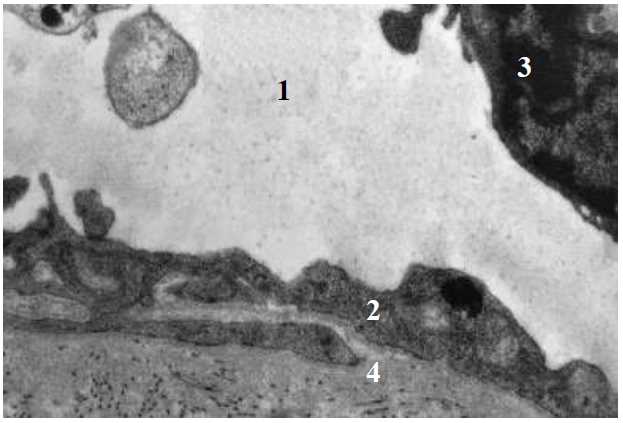

Fig. 5. Ultrastructure of t. intima of iliac artery of a rat in 1 day after modelling of ischemia-reperfusion: 1 – lumen; 2 – endotheliocytes; 3 – thickened basement membrane; 4 – edematous subendothelial connective-tissue layer. TEM. x 4000

In the first day after modelling of reperfusion, pathohistological findings on the light-optical and electron-microscopic levels did not differ from those of the first group: dystrophic changes and evident interstitial edema were seen in the vessel wall being a marker of a hypoxic injury of a specialized tissue. However, on the third day these changes in the second group acquired a mosaic pattern. Along with pathological processes there also occurred adaptive changes in the structures of the vessel wall. In particular, there were noted moderate dilation of the lumen of some vessels, alteration of the organelles of endothelial cells: edema of separate mitochondria, increase in the surface area of nuclei due to invaginations, moderate enhancement of micropinocytosis (Fig. 5). Along with compensatory changes, pathological changes were also found in the endotheliocytes of blood vessels manifested by their edema with their swelling and destruction of separate mitochondria.

Mitochondria were vacuolated, their matrix lucent, cristae disoriented. Cisterns of the cytoplasmic reticulum and Golgi complex dilated. Predomination of signs indicating reactive changes in endotheliocytes was noted including increase in the surface of nucleus due to formation of invaginations of different depth, and evident pinocytic activity of plasmalemma of endotheliocytes.

Simultaneously in some parts disorders in the interendothelial contacts were observed with dilation and edema of the pericapillary space. Electron-microscopic examination of the ultrastructure revealed alterations of endothelial cells, of basement membrane of microcirculatory vessels, pericytes and perivascular space.